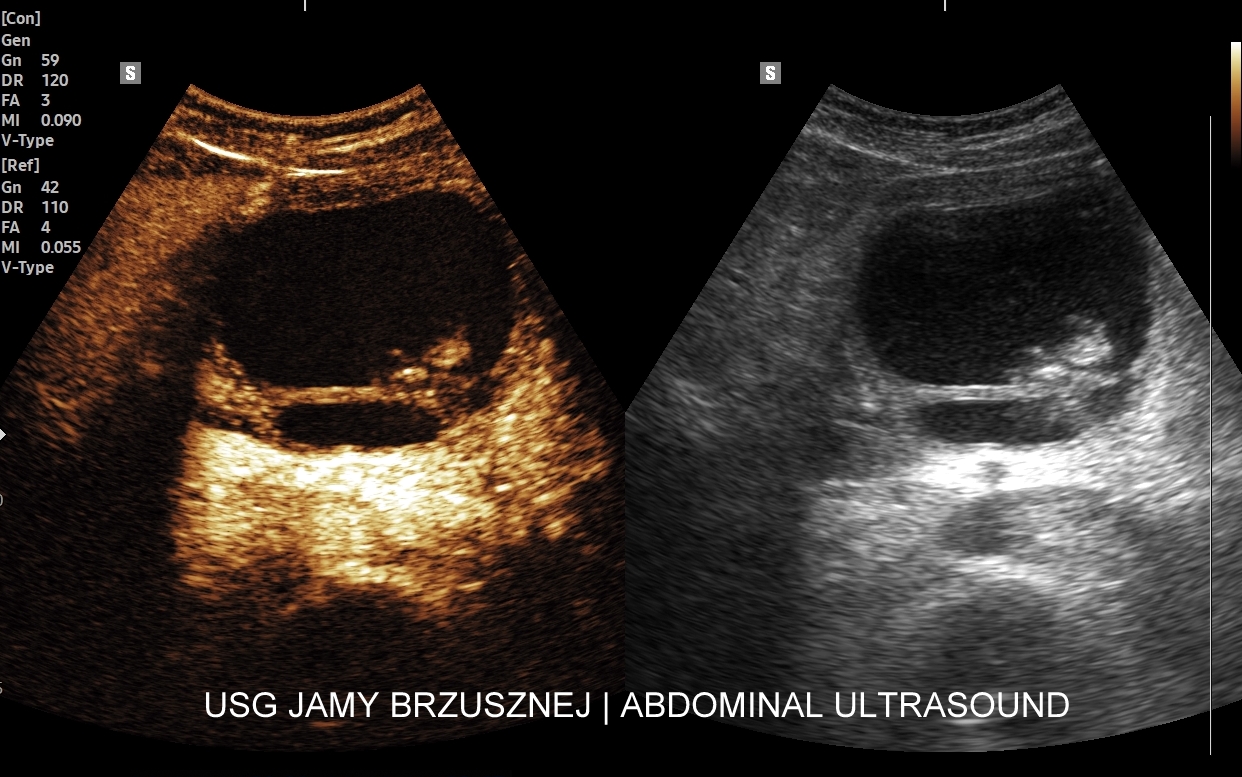

Rozwinięciem standardowego badania USG jamy brzusznej jest badanie multiparametryczne MPUS (ang. multiparametric ultrasound), w ramach którego wykorzystuje się różnorodne, nowoczesne modalności sonograficzne, takie jak tryby mikrounaczynienia MVI, B-flow, elastografię, ilościową ocenę stłuszczenia wątroby QUS, czy tryb Dopplera spektralnego, a to wszystko w celu uzyskania dodatkowej oceny funkcjonalnej i biologicznej struktur, narządów oraz tkanek jamy brzusznej. Obrazowanie MPUS niejednokrotnie poprawia także wizualną ocenę narządów wewnętrznych, czego przykładem jest zastosowanie trybu MVI w ramach bezkontrastowej angiografii sonograficznej naczyń oraz w ocenie guzów nerek. Klasycznymi i najczęstszymi zastosowaniami badania MPUS są jednakże funkcjonalna ocena wątroby w kierunku stłuszczenia, zwłóknienia, zapalenia i nadciśnienia wrotnego, a także ocena żywotności i funkcji nerek.